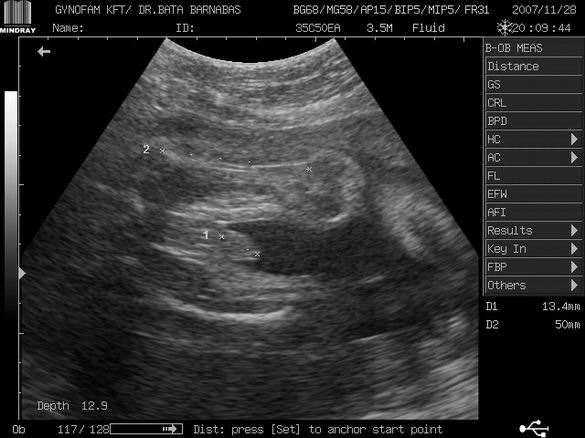

Gergő gyönyörű :wink: , mindene megvan. Szép hosszú combija van, 29 hetesnek megfelelő, a cerkája (mert, hogy azt is megmérte :lol: ) MÁR 1.4 cm!! :P :P

A méhszájam 3000-es, teljesen zárt. A becsült súlya a kisfiúnknak már 1.21 kg!!! Azt mondta szép, nagy babánk lesz!! :shock:

Képet mentettünk pendrive-ra, de csak egy érdemes kukkantásra: a cerkás kép :lol:

Itt a két combikája között ott a cerkája :wink: